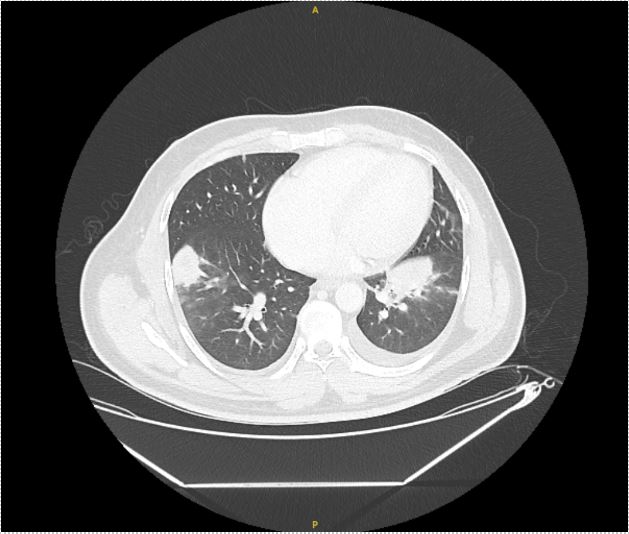

Case Presentation: A 36-year-old male with no significant medical history presented with one week of nocturnal fevers, rigors, cough associated with night sweats and 5 kg weight loss over one month. He immigrated from Guatemala 18 months ago, briefly lived in Arizona and Texas, and has worked as a landscaper locally for the past year. Review of system was negative for chest pain, shortness of breath, rashes, recent illness, or sick contacts. On admission, he had a fever of 39.4°C and was saturating 97% on room air. Physical exam was pertinent for course lung-sounds bilaterally and no skin rashes or ulcerations. Blood work was significant for leukocytosis (13.24 K/uL with neutrophilic predominance). CT Chest showed mass-like opacities in the bilateral lower lobes and left upper lobe, mediastinal and hilar lymphadenopathy, bilateral pleural effusions, and a 6mm right lung nodule (figure 1 and 2), raising concerns for neoplastic, rheumatologic, and/or infectious etiology. Our initial infectious workup, including blood and sputum cultures, HIV testing, tick-borne panel, and endemic mycoses was negative and the patient showed no improvement of symptoms or leukocytosis despite treatment with cefepime and azithromycin. On hospital day 7, bronchoscopy with lymph node biopsy was performed. Fevers persisted despite treatment with cefepime, azithromycin, and minocycline. Further infectious workup for fungal pathogens, Tuberculosis, and Coxiella was negative. Rheumatologic and oncologic workup with ANA, RF, vasculitis panel, and peripheral flow were also negative. On hospital day 14, send out testing for Tularemia IgG and IgM was positive, alongside pathology showing necrotizing granulomas positive for Francisella tularensis DNA. His antibiotic regimen was switched to IV gentamicin and PO doxycycline, leading to immediate symptom improvement on day 2 of treatment. The patient completed 10 days of targeted antibiotic therapy in-patient due to lack of insurance, with rapid resolution of fever, leukocytosis, and symptoms.